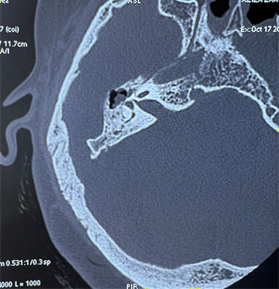

On the ct scan of the temporal bone, the right

ear cavity had a soft tissue density, incomplete filling of the epitympanum and

mesotympanum, by well-defined, encapsulated tissue formations, one of which is

pedicled opposite the jacobson's nerve, thining of the tegmen tympani,

ossicular lysis, fistula between the upper semicircular canal and the tympanic

cavity and mastoid cell filling (figure

4).

Figure 4: ct scan of the temporal bone in coronal and axial cuts: showing soft tissue density within the right middle ear cavity, pedicle tissue formation opposite the jacobson nerve, ossicular lysis, fistula between the upper semicircular canal and the tympanic cavity.